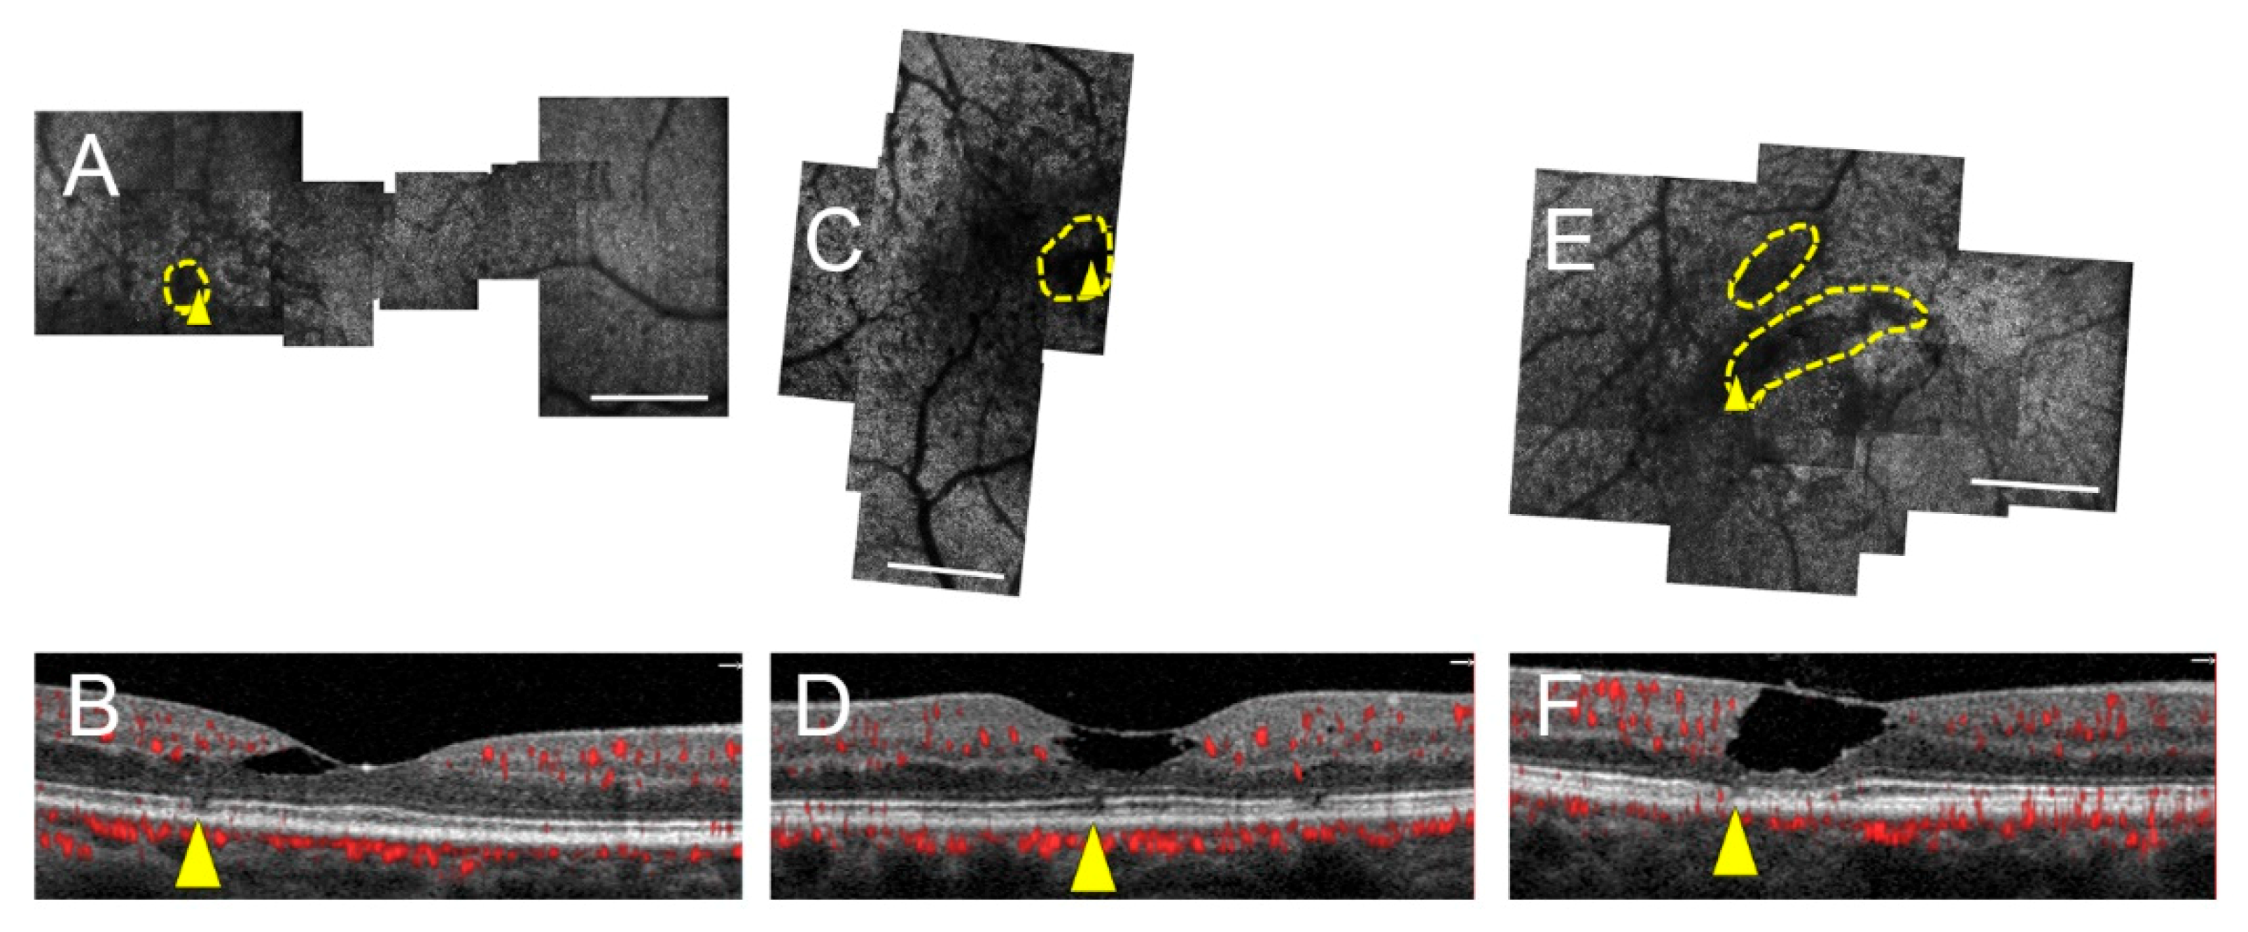

Topographic Relationship between Telangiectasia and Cone Mosaic Disruption in Macular Telangiectasia Type 2

3. Results